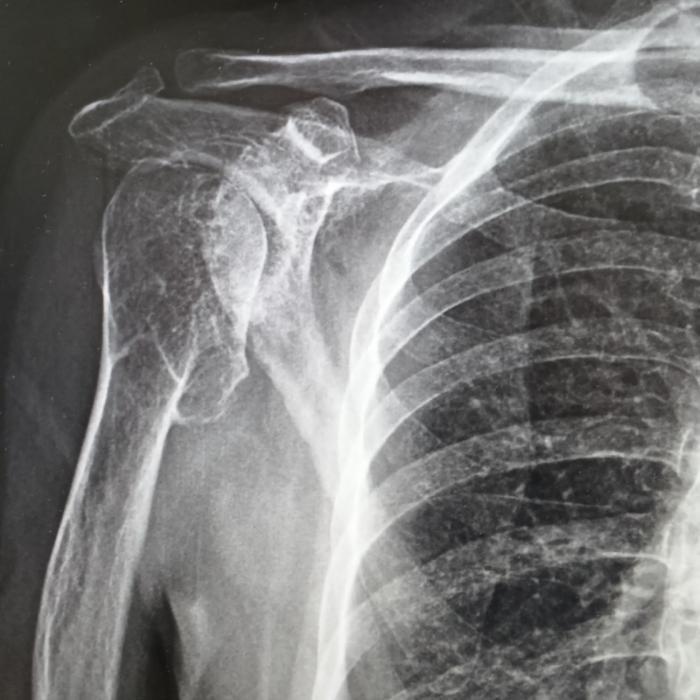

患者右肩疼痛已超過5年,日常梳頭、穿衣均受影響。多次接受針灸、外敷藥等保守治療效果不佳。2025年10月MRI檢查顯示:右肩關(guān)節(jié)嚴(yán)重退行性變,肱骨頭塌陷變形伴多發(fā)骨贅,關(guān)節(jié)腔積液及滑膜炎,同時(shí)存在盂唇損傷與肩袖損傷,岡上肌撕裂伴嚴(yán)重退變。

在成都市第三人民醫(yī)院評(píng)估后明確診斷為右肩關(guān)節(jié)重度骨性關(guān)節(jié)炎伴肩袖損傷?紤]其關(guān)節(jié)結(jié)構(gòu)破壞重、功能需求高,團(tuán)隊(duì)為其制定反式人工肩關(guān)節(jié)置換方案。